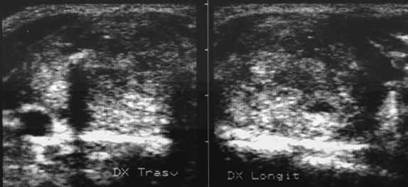

CalcificaRi IN parenchimUL tiroidIAN

Femeie de 74 ani. Calcificari grosolane in lobul drept.

Barbat de 73 ani. Microcalcificari in lobul drept

intr-o gusa nodulara voluminoasa